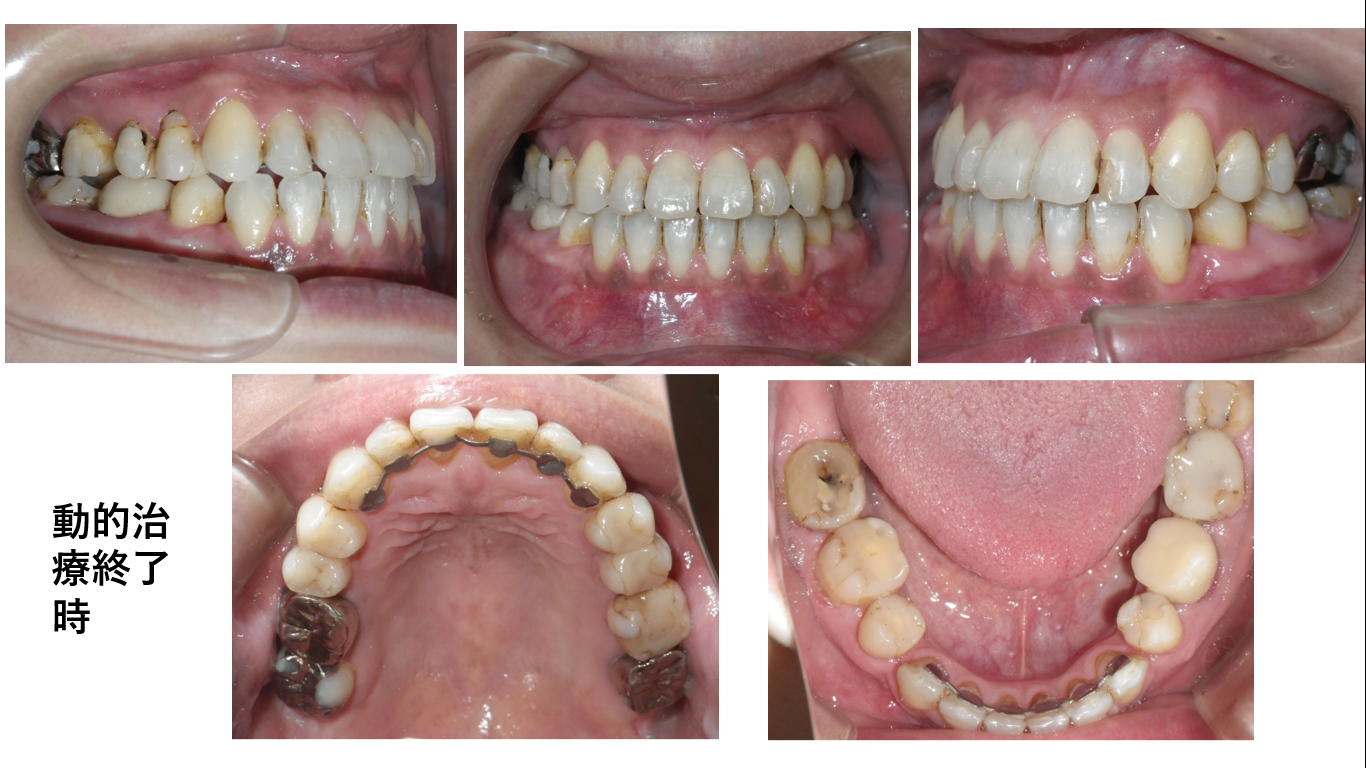

矯正症例119 Skeletal classⅢ、骨格性下顎前突、反対咬合、能代市、北秋田市、秋田市、大館市

初診時35歳8か月、性別:女性、抜歯部位:下顎左右4番、治療期間3年10か月、治療費総額98万(税込み)

上は初診時の口腔内写真です。右上4、5番、左上4番が反対咬合です。大臼歯は咬頭対咬頭の咬合です。

上の写真は、左が初診時、右が動的治療終了時の横顔です。初診時の横顔は悪くないので手術はしないで歯並びを治しました。